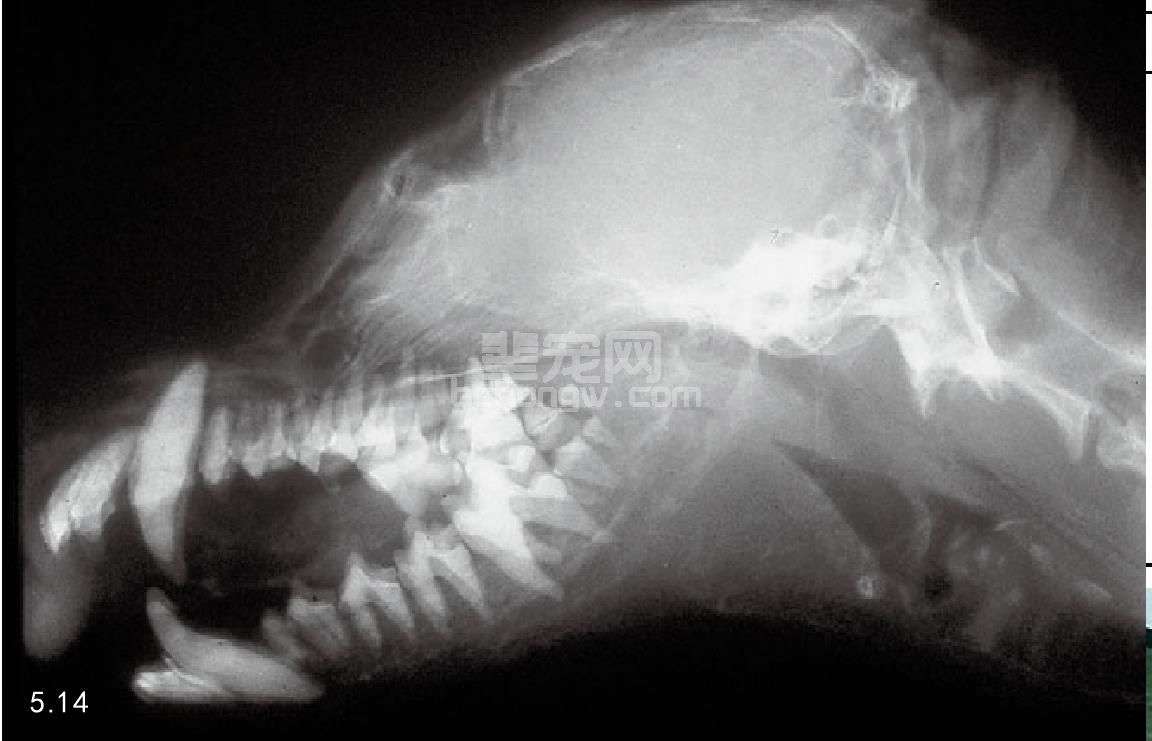

图5.14 放射学检查图5.12犬的骨骼显示骨密度很低。

进行身体检查时,多数患病动物出现体温过低并有“尿毒症气味”口臭。出现氮质血症,触诊口腔黏膜,一般会发现有潜在的溃疡。病程长久其下颌极具弹性(橡皮颌),这种情况并不常见(图5.13)。对于年轻的犬,其下颌和上颌骨可能会出现肿胀及牙齿松动(图5.14)。触诊肾脏异常,小、硬、多块状、大等。高血压多见。